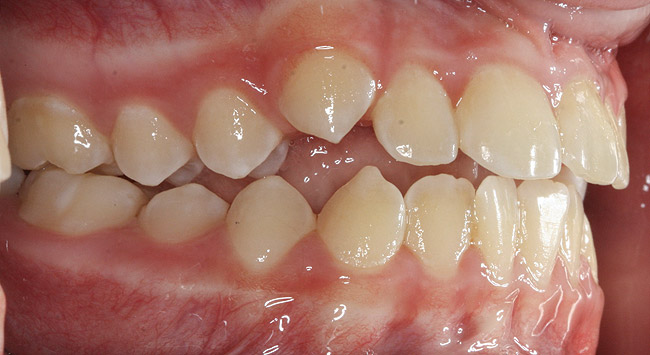

(3.) Three-year-old with a history of snoring, bruxing, and thumbsucking. Her father and brother were both diagnosed with OSA.

Figure 3

(4.) Patient presents bilateral crossbite and significant attrition. Father assists in retraction.

Figure 4